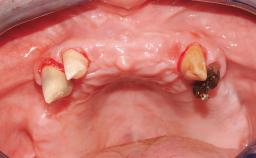

A 65-year-old female patient with a failing residual maxillary dentition and a complete mandibular removable denture was referred for consultation and treatment. The patient’s chief complaint was that her upper residual teeth were mobile and she was unable to chew. The patient also asked us to improve the esthetic appearance of her smile. The patient’s desire was a stable and comfortable dentition in both jaws, and she specifically asked for a fixed rehabilitation. The patient reported a history of recurrent caries, endodontic complications, and periodontal disease as main reasons for previous teeth extractions. The anamnesis was negative for bruxism and TMJ disorders. The patient had no systemic diseases, was not on any medication,and did not smoke. The extraoral examination revealed a medium lip line, a wide diastema between the two central incisors (which, according to the patient, had appeared recently), and a partial collapse of the perioral soft tissues, probably due to loss of the correct vertical dimensions.

Bone Volume Deficient horizontally, allowing simultaneous augumentation